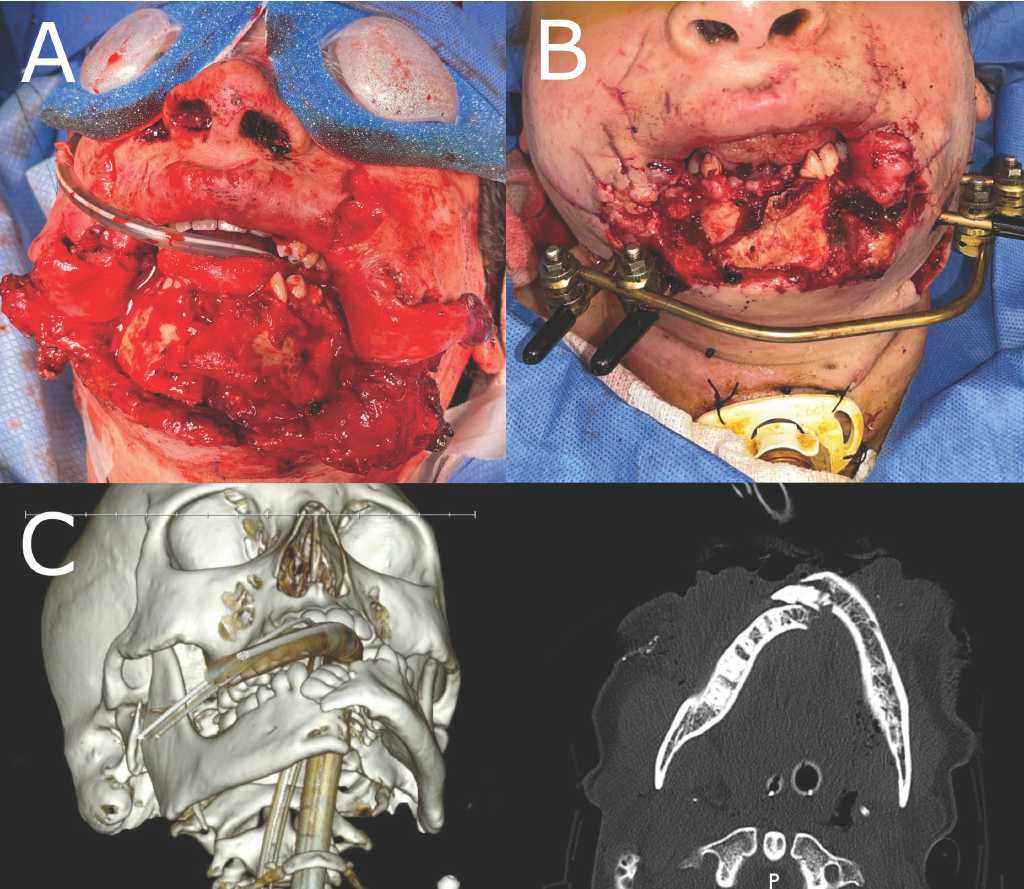

Our patient is a woman in her early thirties who tripped while igniting a large, professional-level aerial shell firework. As she stumbled, the shell deployed, hitting the patient directly in the chin and detonating, resulting in massive trauma to her lower face. At presentation, the patient was intubated via tracheostomy, her wounds were debrided, and shell fragments were removed. In addition to lacerations across the face and neck, she sustained total loss of soft tissue over the chin, exposing a large portion of the anterior mandible. The mental nerves were lost bilaterally. There was also a full thickness defect in the cutaneous and mucosal portions of the lower lip, well beyond the oral commissures (Figure 1A). Moreover, the patient suffered a comminuted mandibular fracture in the parasymphyseal region (Figure 1C). A section of the anterior alveolar bone of the mandible was lost, which included the lower incisors and right lower cuspid tooth. An external fixator and intermaxillary fixation of the remaining teeth were applied after debridement to maintain reduction of the fracture and to help maintain occlusion of the remaining dentition (Figure 1B). The wounds were cleaned and covered, and the patient underwent her first repair procedure 15 days later.